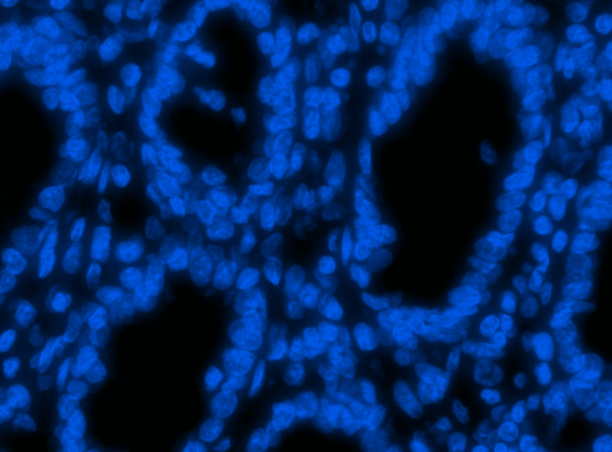

We train and test SP-CNN and TSP-CNN on two colon cancer datasets: 1) publicly available UW Dataset [5] which includes H&E stained histology images of colorectal adenocarcinomas. There are a total number of nuclei marked at the nucleus center (please refer to Sec. VII.A. of [5] for more information). Our choice of the UW Dataset is because it represents real-world challenges such as overlapping nuclei and contains other shapes that are often confused with nuclei. Further, it is one of the few publicly available datasets that is widely used in many recent deep learning-based nuclei detection methods [5, 19, 46], 2) a new dataset carefully prepared and labeled manually by medical experts at the Center for Molecular Immunology and Infectious Disease, Penn State University. We call it the ‘PSU Dataset’ and it includes images of colon tissue from pigs at a resolution of m/pixel. Formalin fixed paraffin embedded pig colon sections were deparaffinized and stained with fluorescent DNA stain DAPI (4’,6-diamidino-2-phenylindole) to visualize the cells as described in [47]. The selected images represent cross-sectional view of the colon epithelial cells. It also comprised of areas with artifacts, over-staining, and failed auto focusing, to represent outliers normally found in real scenarios. A total number of nuclei are annotated manually by an expert. For reproducing research results, we have made this dataset publicly available at the SP-CNN web-page [29]. Sample images from both datasets are shown in Fig. 8.